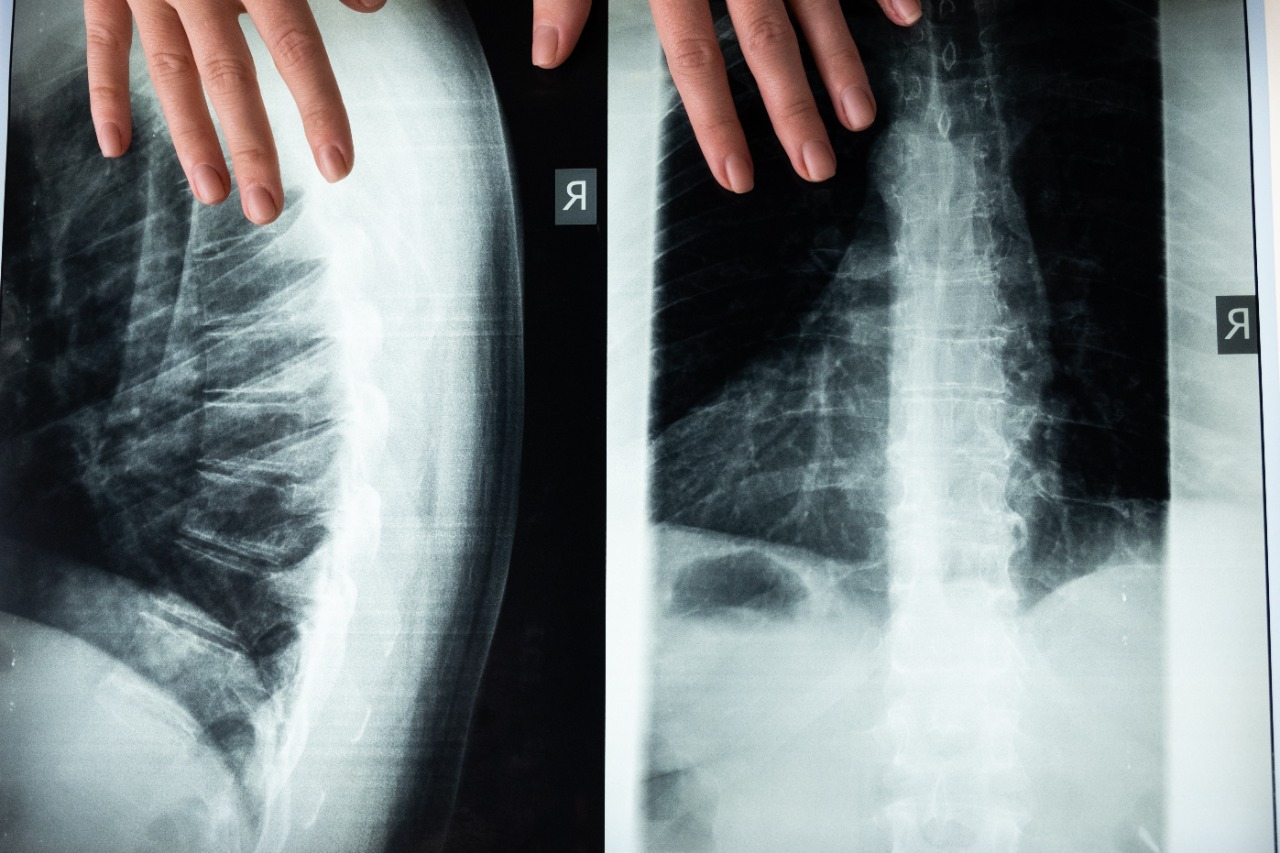

La médula espinal es una estructura cilíndrica aplanada de tejido nervioso que se encuentra en el conducto raquídeo de la columna vertebral, es la encargada de transmitir impulsos nerviosos a los nervios raquídeos que van desde el encéfalo a todo el cuerpo.

La médula espinal se extiende desde la base del cráneo hasta un poco por debajo de la mitad de la espalda y funciona a través de 2 formas: una es enviando las sensaciones hacia el cerebro para evaluar los movimientos de regreso hacia el resto del cuerpo (cuello, tronco y extremidades).